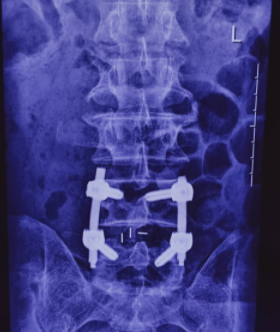

经专家会诊,决定对该患者实施微创经椎间孔入路腰椎椎体间融合术(MIS-TLIF),这也是我院首例微创经椎间孔入路腰椎椎体间融合术(MIS-TLIF)。手术过程顺利,术后患者生命体征趋于平稳、精神状态明显好转,术后3天就能拔管下地。

传统后路的椎间融合术(PLIF),术中需要腰椎两侧广泛的椎旁肌剥离,导致椎旁肌术后一定程度的失神经改变,发生纤维化,表现为腰痛、无力;需要切除两侧更多的后方结构,客观上削弱了腰椎节段的稳定性,甚至加速了邻近节段退变,术中需要对两侧的神经根进行牵拉,增加了神经根损伤的几率。微创通道下的TLIF手术避免了对椎旁肌肉进行骨膜下剥离,减轻了对椎旁软组织的损伤,保留了后方韧带复合体,出血量少,住院日短,术后并发症发生率低。